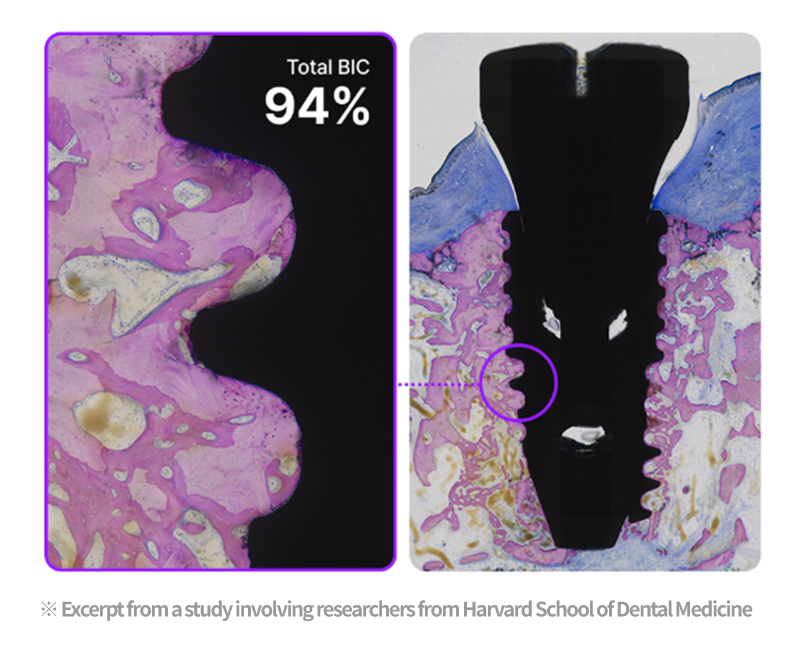

94% Bone Integration in Just 4 Weeks

With faster osseointegration, a 94% bone integration rate was reported in a short period. (Based on a publication involving Harvard researchers)

Harvard dental research confirms

the excellent performance of plasma implants

According to research by Harvard School of Dental Medicine, plasma implants showed excellent bone integration, reduced bone loss, shorter healing time, and improved long-term stability.

Plasma treatment helps remove impurities left on the implant surface and improves surface hydrophilicity for better biocompatibility. Thanks to these benefits, plasma technology helps improve implant success and serves as a key factor for faster recovery.